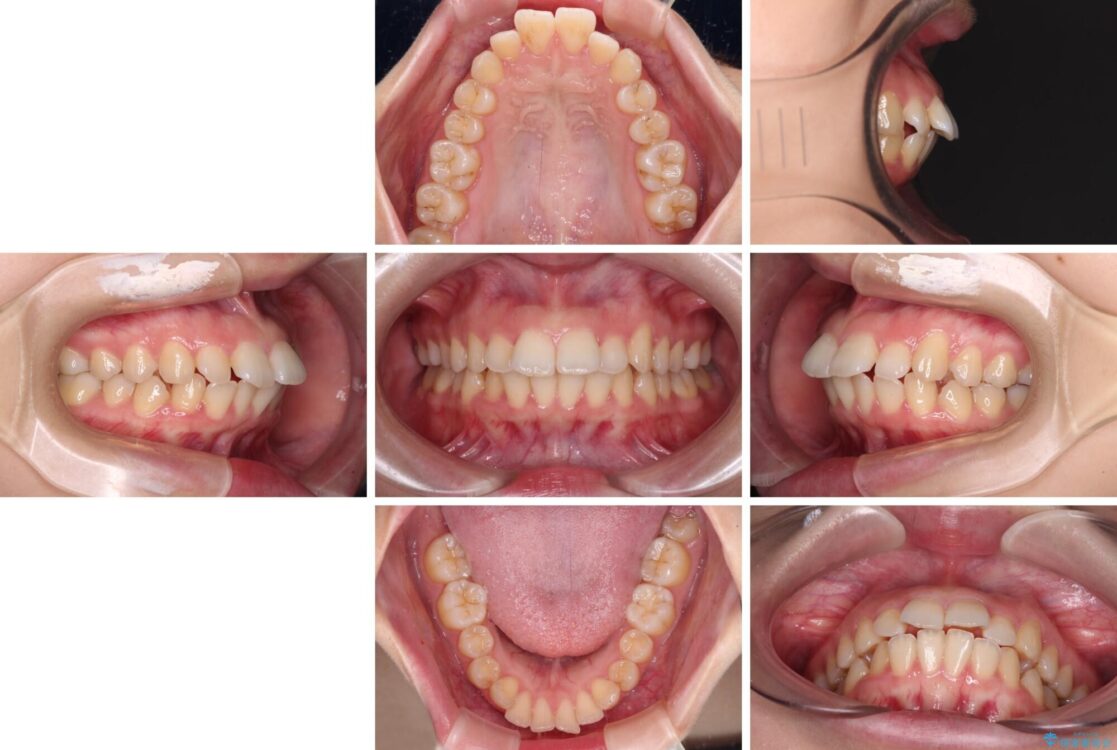

治療前

• 【モニター】口が閉じられない ワイヤー装置での抜歯矯正 治療前画像